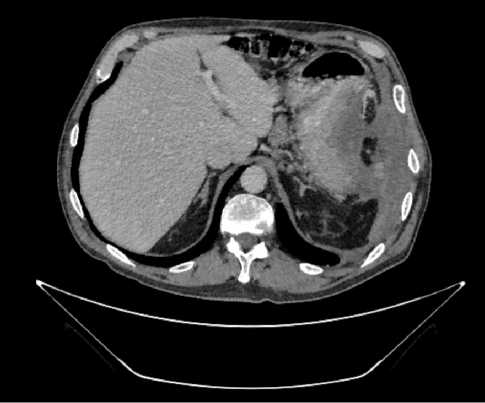

В результате обследования был установлен диагноз рака антрального отдела желудка (c)T4аN3вM1. По решению онкологического консилиума, учитывающего молекулярно-генетический профиль опухоли, а также возраст пациента, выраженность сопутствующей патологии (в анамнезе острое нарушение мозгового кровообращения (ОНМК), острый инфаркт миокарда (ОИМ), фибрилляция предсердий (ФП), постоянная форма), ограничивающей проведение ПХТ, была начата ИТ 1 линии пембролизумабом. С сентября 2019 г. по декабрь 2021 г. проведено 29 циклов ИТ 1 линии по схеме пембролизумаб в монорежиме с максимальным эффектом частичный регресс (рис. 4). Осложнений лечения не зарегистрировано.

Рис. 4. Частичный регресс по данным компьютерной томографии органов брюшной полости на фоне иммунотерапии пембролизумабом у пациента 81 года с диагнозом метастатический рак желудка с признаками микросателлитной нестабильности (декабрь 2021 г.; выживаемость без прогрессирования составила 25+ мес.)

Fig. 4. Partial response according to abdominal CT scan during immunotherapy with pembrolizumab in an 81-year-old patient diagnosed with MSI-H metastatic gastric cancer (December 2021; progression-free survival was 25+ months)

Для оценки метаболической активности остаточной опухолевой ткани выполнено позитронно-эмиссионная томография, совмещенная с компьютерной томографией (ПЭТ-КТ) в марте 2022 г., по результатам которого выявлено умеренное повышение уровня метаболической активности в проекции выходного отдела желудка и двух ЛУ брюшной полости, без значимой динамики в сравнении с предшествующим исследованием.

Для морфологической оценки патоморфологического регресса выполнена эзофагогастродуоденоскопия — эндоскопические признаки полного регресса опухоли. По результатам гистологического исследования, опухолевых клеток не выявлено.

Пациент находится под динамическим наблюдением без признаков прогрессирования процесса по настоящее время (выживаемость без прогрессирования составила 25+ мес.).